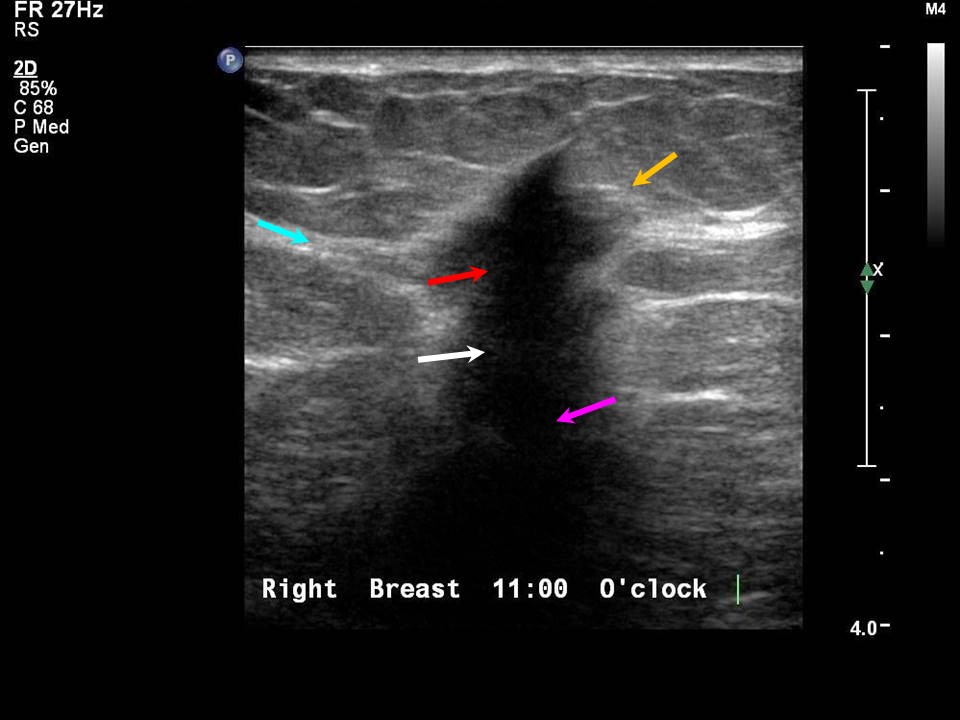

US shows (A) hypoechoic solid mass with irregular spiculated margins at Spiculated Margins The classic description of a breast cancer is a mass with an irregular shape and spiculated margin (fig. They describe the extent and possible infiltration of the mass into the surrounding breast parenchyma. It has been our experience that. Click on the pictures to. Spiculated margins are seen in malignant masses. Spiculated masses are defined as masses with lines radiating. Spiculated Margins.

From www.researchgate.net